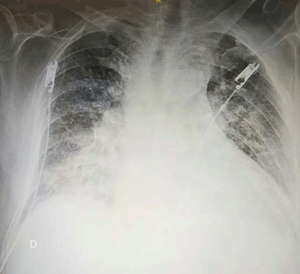

En la radiografía de tórax (figura 2) se observó un índice cardiotorácico aumentado y en los campos pulmonares, opacidades inhomogéneas bilaterales, a predominio de los campos inferiores y un patrón reticular bilateral.

Figura 2: Opacidades pulmonares inhomogéneas bilaterales, a predominio de los campos inferiores y patrón reticular bilateral.